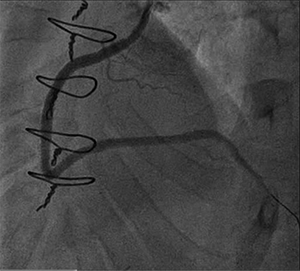

In the interim, the patient reported improvement in his symptoms. He returned 2 months after the initial procedure for follow-up angiography, which revealed that the subintimal space remained open (figure 2). Antegrade wiring then progressed to the distal RCA and, subsequently, stenting was performed (figure 3).

Figure 3. Final angiography after stenting